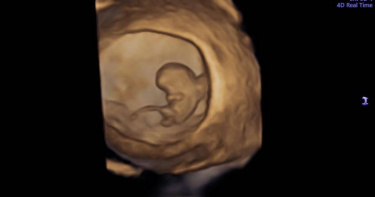

胎兒「身上1根」長到逆天!婦科名醫給答案:不是GG 全網笑翻

婦產科名醫蘇怡寧經常在粉專解答孕媽咪的疑問,擁有許多忠實粉絲,他今(16日)在臉書PO出1張寶寶的超音波照片,只見胎兒身體上有1根凸出物顯得特別長,很多人都會認為是生殖器,因此他特別說明「請不要隨便看到一根東西就說是GG」,因為那其實是臍帶。貼文引發網友討論,不少人笑稱「從小就這麼優秀,長大還得了」。蘇怡寧今日在臉書粉專「蘇怡寧醫師愛碎念」分享照片,並發文「各位同學,請不要隨便看到一根東西就說是雞雞,不管你想不想要,就不是!這根是臍帶,謝謝!」只見胎兒已略為成行,且身體上有1根凸出物,顯得特別長,確實很容易被誤認為男性的生殖器。畫面引發討論,不少網友留言「從小就這麼優秀,長大還得了」、「哪那麼長」、「如果是GG,這孩子未免太傑出了吧」、「這些家長要是胎兒雞雞這麼長不擔心有異常嗎」、「是雞雞他可以參加世界紀錄了」、「這麼長的gg是正常人嗎」、「爸媽希望自己的兒子是世界長的尺寸」、「就算是,比例也太長」。另外,也有人笑稱「突然讓我聯想到周星馳韋小寶電影中,吳孟達一看到什麼就喊GG」、「我也都是自己當醫生,第一胎自以為看到雞雞,結果是臍帶。第二胎以為是母的,結果醫生說兩腿中間有東西。還好我不是醫生,不然會被砸招牌」、「可能她第一胎已經是男寶寶,看到這個會驚喜」。